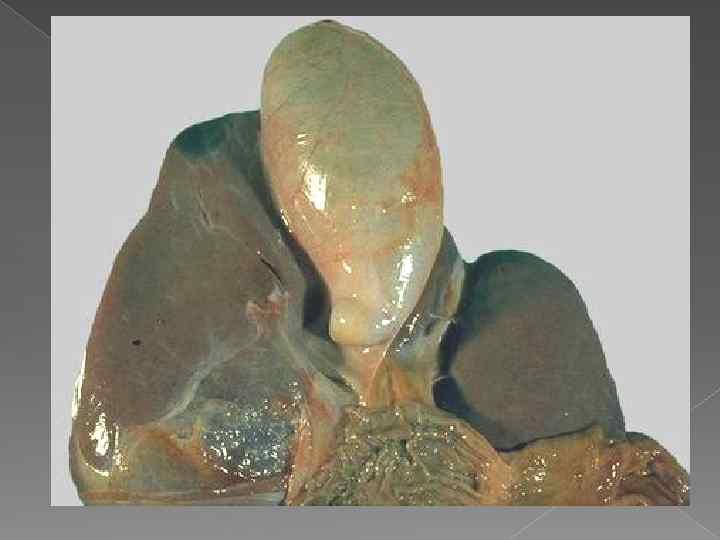

ОСЛОЖНЕНИЯ ХОЛЕЦИСТИТА Множ естве нные спайк и желчн ого пузыр я; макро препа рат. Множественные спайки желчного пузыря

ОСЛОЖНЕНИЯ ХОЛЕЦИСТИТА Множ естве нные спайк и желчн ого пузыр я; макро препа рат. Множественные спайки желчного пузыря